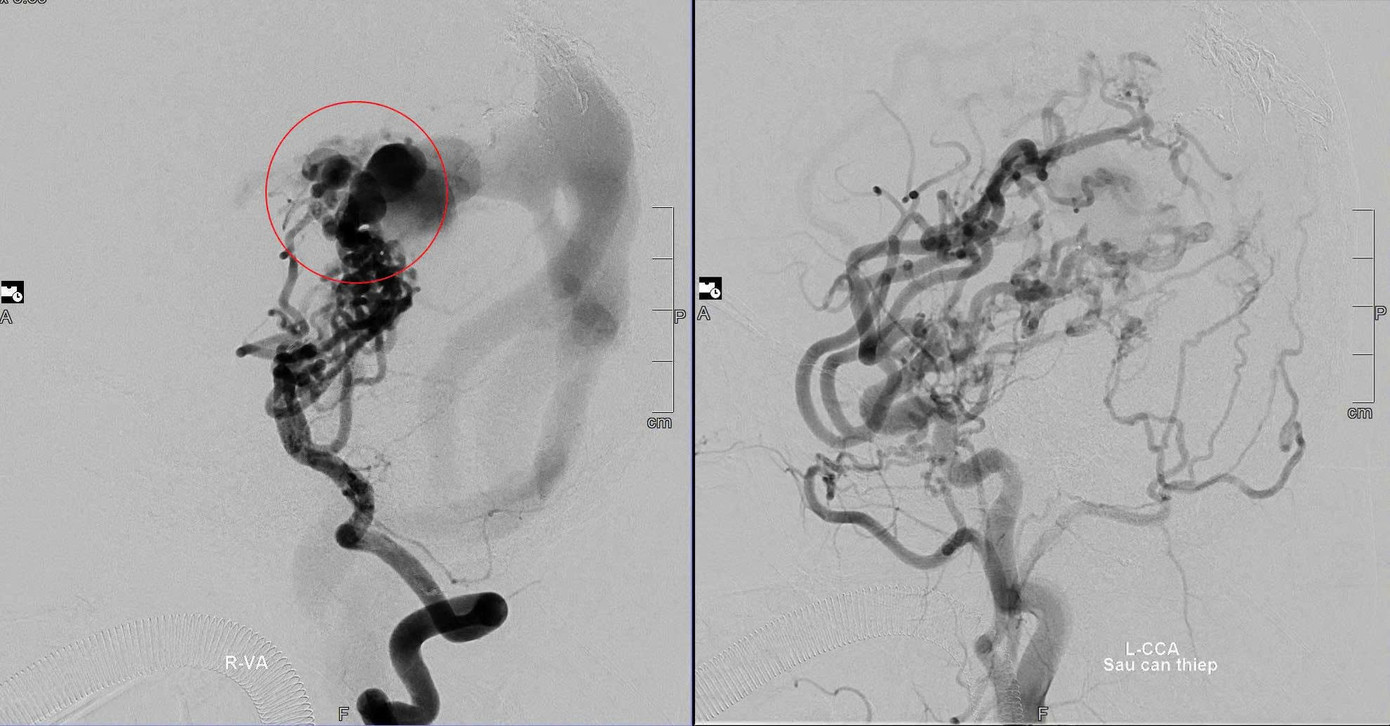

Hình ảnh mạch máu não của bệnh nhân trước và sau khi được các bác sĩ can thiệp.

Theo bệnh sử, ngay khi vừa chào đời tại Bệnh viện Nhi Đà Nẵng, bé D. rơi vào tình trạng tím tái, suy tim cấp và suy hô hấp nặng. Kết quả chẩn đoán cho thấy trong não bé có khối dị dạng mạch máu bẩm sinh với nhiều động mạch nuôi phức tạp, lưu lượng máu chảy qua rất cao. Hình ảnh kiểm tra ghi nhận cấu trúc mạch máu não của bệnh nhi như một “cây cụt tán”.